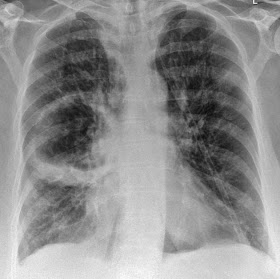

Patient has brought the following X ray with him that was done a day before:

Chest x-ray demonstrates a large intrapulmonary cavity with an irregular air/fluid level interiorly. The wall of the cavity is ill-defined, ranging from very thin and smooth laterally to somewhat nodular superomedially.

The Patient is diagnosed as a case of Lung Abscess

Chest X ray will often show a cavity with a fluid level.